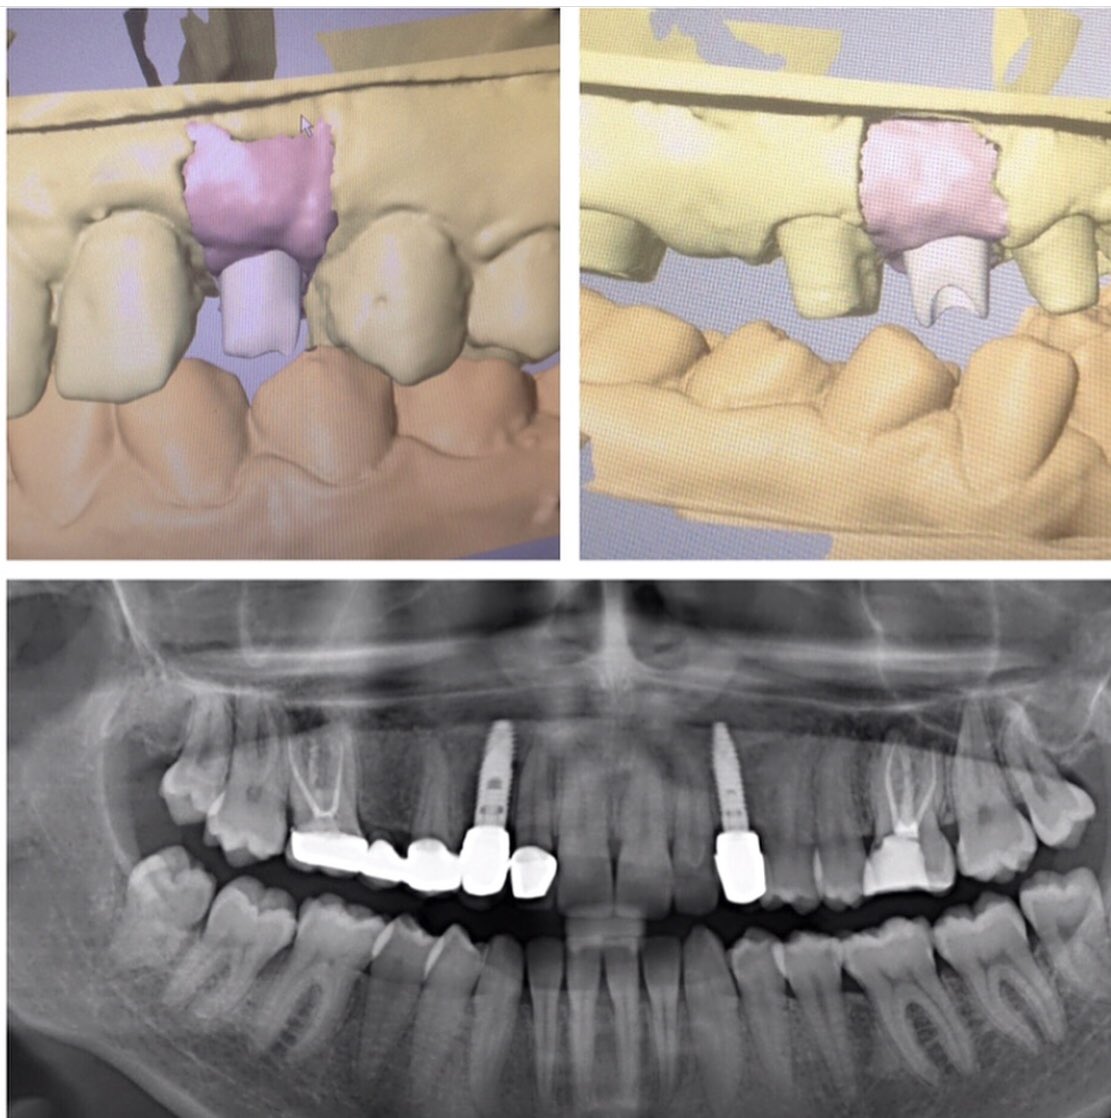

Uzun bir yolculuğu tamamladık. Gömülü köpek dişlerini damaktan alıp aynı seans implant ameliyatını tamamladık. İyileşme sonrasında implant üst yapısını CAD-CAM ile planlayıp zirkon alt yapılı protezini ürettik.